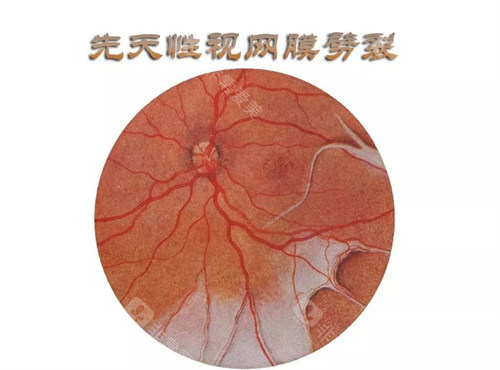

作为首都医学大学附属北京同仁医院眼底病科的“定海神针”,他擅长复杂眼底病诊疗,尤其对视网膜脱离、糖尿病视网膜病变等疾病的手术处理堪称业内标杆。